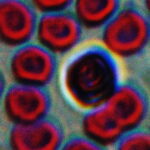

顕微鏡写真。40倍

100倍です。